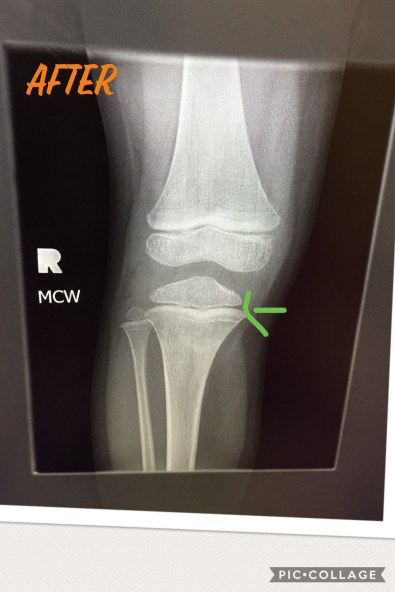

The fact that the two darker lines run parallel, tells them that his legs are growing symmetrically so the growth plate is a-ok

So after waiting 45 minutes (insert more whining from Young Jedi), we got our 3 minutes with Dr Fluffy Unicorn (don’t get me started on that! Even his nurse missed the check-up, it was so short!) where we learned that his growth plate was NOT impacted by the fracture. Can I get a hallelujah!?! Seriously, we needed that small miracle.